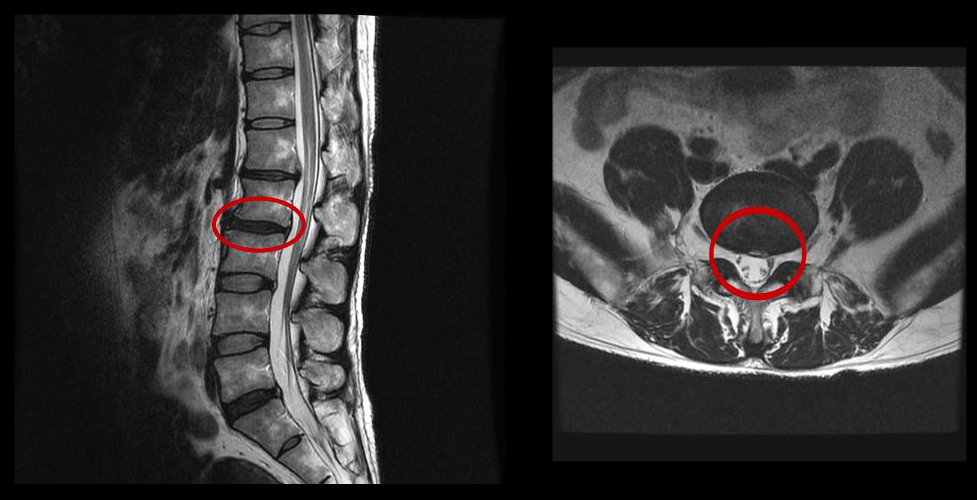

그런데 이 환자분의 MRI를 보면 여러 마디에 퇴행성디스크가 있습니다.

<3-4번>

이 환자분은 MRI상으로 거의 대부분 마디의 디스크가 퇴행되고 수핵이 밀려나와 있으며, 정상적인 허리 마디는 4-5번 하나 정도입니다. 그렇기 때문에 MRI만 보면 아마 대부분의 병원에서 허리디스크탈출 또는 퇴행성디스크로 인한 허리통증 및 다리통증으로 진단하고 치료할 것입니다. 이분도 그래서 20년간 그런 치료를 무수히 많이 받았으나 그 어떤 치료도 별 도움이 되지 않았습니다.

이 환자분처럼 오랜 기간 만성적인 허리통증이 있고, 엉덩이가 저리면서 심지어는 양쪽 다리저림까지 있는 환자분들이 많습니다. 그런데 이 환자분의 MRI를 보면 여러 마디의 퇴행성디스크, 디스크탈출, 황색인대의 두꺼워짐, 후관절의 퇴행 등 다양한 병변들을 가지고 있는 걸 볼 수 있는데요. 그렇기 때문에 많은 병원에서 이분을 디스크로 진단하고 거기에 따른 치료가 이루어졌습니다. 그러나 저희가 보기에는 이분의 MRI상으로 보이는 여러 마디의 디스크 문제가 이 환자분이 갖고 있는 증상을 설명할 수 없었습니다.